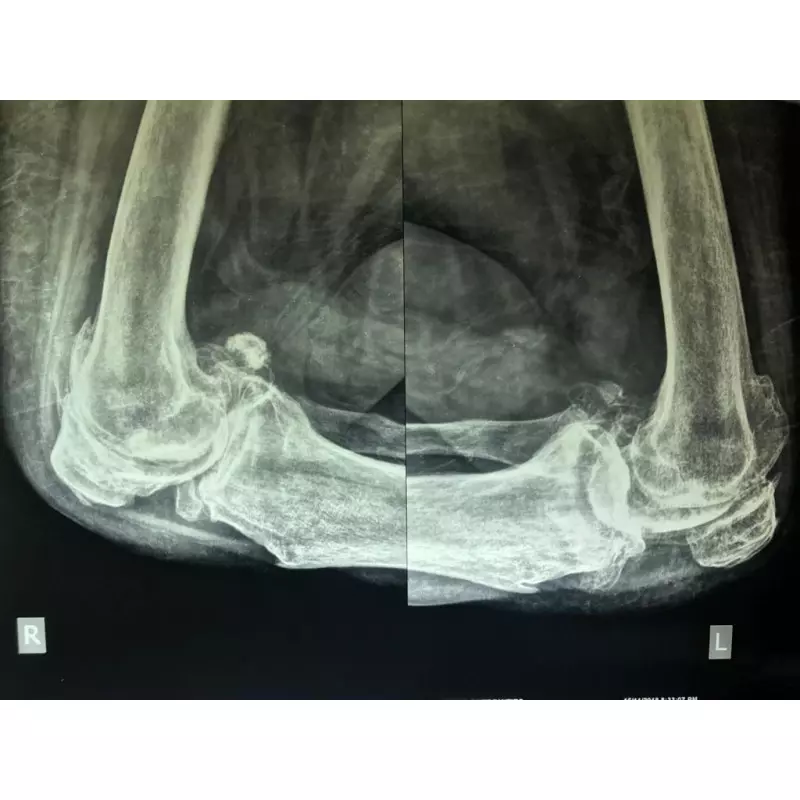

Details of Single Sitting Total Hip And Knee Replacement F/75 Obese